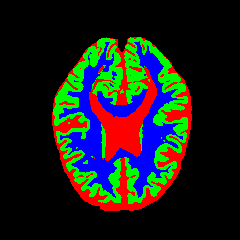

• OASIS-1 [34]: Derived from the Open Access Series of Imaging Studies, this dataset comprises T1-weighted MRI scans from 421 subjects (aged 18–96). The images were acquired with a resolution of 176×208176\times 208 pixels and a slice thickness of 1.25 mm (TR=9.79.7 ms, TE=4.04.0 ms, TI=2020 ms). Following standard protocols, we utilize the provided manual segmentation masks for Cerebrospinal Fluid (CSF), Grey Matter (GM), and White Matter (WM).

7 Qualitative Evaluation

Fig. 8 and Fig. 10 provide qualitative comparisons on the OASIS-1 and MRBrainS13 datasets, respectively. It is visually evident that the baseline predictions (c) and standard augmentations (e.g., (d), (g), (i)) frequently suffer from noisy artifacts, blurred boundaries, and mis-segmentation of intricate anatomical structures. In stark contrast, our ”Ours+” enhanced methods (e.g., (e), (h), (k)) consistently produce segmentation maps that are visibly cleaner, more spatially coherent, and demonstrate significantly sharper adherence to the Ground Truth (b). This superior fidelity is particularly noticeable in the complex sulcal patterns and holds true across all three backbones (rows), confirming that our framework yields more robust and anatomically plausible results.